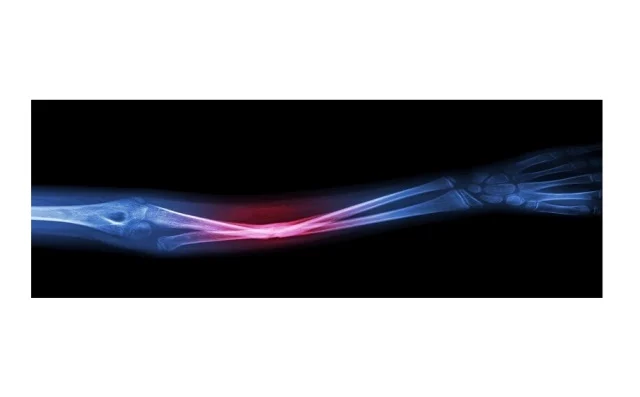

تعلن مجموعة من الباحثين من جامعة سونغ كيون كوان عن تطوير نظام طباعة موضعي ينتج مواد العظام مباشرة في موقع الجراحة، باستخدام جهاز يشبه مسدس الغراء الساخن لعلاج العظام. ويسمح النظام بإنتاج سقالات عظمية لحظياً وبشكل مباشر دون الحاجة إلى تحضيرات ما قبل الجراحة مثل التصوير والنمذجة وعمليات التشذيب. كما يتيح النظام مطابقة تشريحية دقيقة حتى في العيوب المعقدة، مما يعزز إمكانية الإصلاح المباشر في غرفة العمليات.

يشرح جونغ سونغ لي من جامعة سونغ كيون كوان، المؤلف المشارك في الدراسة التي نشرت في مجلة Device، أن تقنياتهم تقدم نهجاً مميزاً لتطوير نظام طباعة موضعي لتصنيع وتطبيق سقالة لحظياً وبشكل مباشر في موقع الجراحة. يتيح هذا النهج مطابقة تشريحية دقيقة حتى في العيوب غير المنتظمة أو المعقدة دون الحاجة إلى تحضيرات قبل الجراحة مثل التصوير والنمذجة. يعمل الجهاز عند درجات حرارة تقل عن 60 درجة مئوية مقارنة بمسدس الغراء التقليدي. طور الفريق مادة تشبه العظام تتكون من هيدروكسيباتيت يشكل 50% من حجم العظم البشري إضافة إلى بولي كابرولاكتون كمواد بلاستيكية حرارية، مع احتواء الخليط على مركبين مضادين للبكتيريا لمنع العدوى، ويؤكد لي أن نجاح هذه الخطوات قد يجعل النهج حلاً عملياً وفورياً لإصلاح العظام مباشرة في غرفة العمليات.